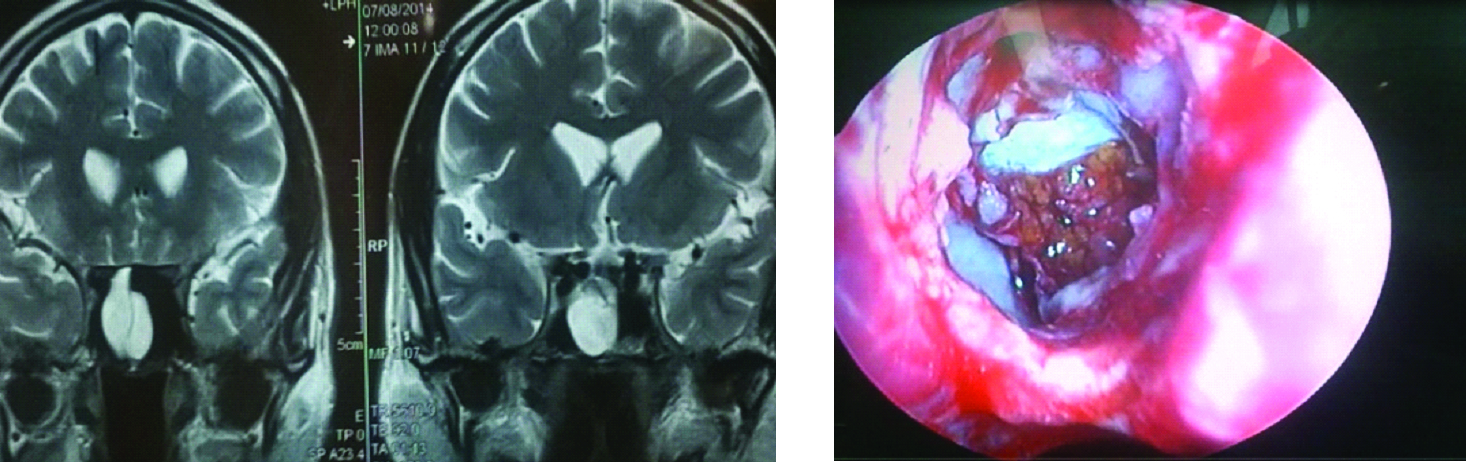

ВВЕДЕНИЕ В настоящее время в связи с распространением лучевых (МРТ, КТ) и визуальных (эндоскопия) методов диагностики наблюдается увеличение количества случаев изолированного сфеноидита [1, 2, 3]. Удельный вес изолированного сфеноидита в общей структуре заболеваний околоносовых пазух (ОНП), по данным литературы, составляет не более 5% [4, 5, 6]. Однако абсолютные цифры с учетом огромного количества случаев воспалительной патологии ОНП могут быть весьма значительными. В структуре синуситов все больше резистентных (устойчивых к лечению) форм, в том числе грибковых [7]. Данные о распространенности патологии весьма скудные, в структуре статистической отчетности стационаров и поликлиник сфеноидит как самостоятельная нозологическая форма отражается крайне редко. В то же время относительно невысокая распространенность нередко обусловливает пассивную позицию специалистов при дифференциальной диагностике поражений клиновидной пазухи (КП). Основное место в дифференциальной диагностике у данной группы пациентов занимают компьютерная томография (КТ) и магнитно-резонансная томография (МРТ). Однако трактовка результатов исследований не всегда однозначна и может приводить как к гипердиагностике, так и, наоборот, к гиподиагностике сфеноидита, выражающейся в недооценке данных лучевой диагностики и обьективной картины и нередко приводящей к развитию хронических и осложненных форм. Пациенты направляются к лор-врачу только после длительного, безуспешного лечения у специалистов смежных специальностей, что влечет высокий уровень гиподиагностики сфеноидита и наличие осложненных форм [8]. Дифференциальная диагностика патологического процесса в пазухе на дооперационном этапе чрезвычайно важна, поскольку необдуманное вмешательство может вызвать тяжелые и даже фатальные осложнения [9, 10]. От 5% до 30% всех изолированных поражений клиновидной пазухи составляют пациенты с неинвазивной грибковой формой [11, 12]. Для хронического сфеноидита характерно латентное (скрытое) течение, которое не всегда диагностируется на ранних стадиях [13, 14]. По данным ряда исследователей, частота патологических находок в клиновидной пазухе при аутопсии лиц, прижизненный диагноз «сфеноидит» у которых не был установлен, составляет от 10% до 68% [15, 16]. Очень важно изучение вопросов ремоделирования в клиновидной пазухе, в том числе явлений остеита при грибковых формах [17]. Осложненное течение изолированного сфеноиди-та - нередкое явление, при этом основным фактором развития осложнений является несвоевременная диагностика. Наиболее часто встречаются осложнения, связанные с вовлечением в патологический процесс глазодвигательных нервов, в особенности VI пары - n. abducens [4, 9, 16]. В литературе можно встретить наблюдения инвазивных, генерализованных форм грибкового сфеноидита с быстрым развитием офтальмологических, интракраниальных и системных (септических) осложнений [7, 12, 14]. Тактика лечения при изолированных поражениях клиновидной пазухи, по данным литературы, различная. Часть авторов считает наличие изолированного сфеноидита, особенно грибковых форм, мукоцеле, абсолютным показанием к операции. Другие авторы при отсутствии осложнений начинают с консервативной терапии [1, 3, 11, 12]. Задачей хирургического лечения у таких пациентов является не только купирование воспалительного процесса, но и создание условий для адекватной вентиляции пазух и предотвращения возможного рецидива. В то же время вопросы дифференцированного подхода к хирургическому лечению недостаточно освещены в научной литературе и носят преимущественно описательный характер. ш ЦЕЛЬ Провести анализ случаев изолированного поражения клиновидной пазух и выявить основные особенности и ошибки при дифференциальной диагностике на догоспитальном этапе. ш МАТЕРИАЛ И МЕТОДЫ В работе приведены данные о лечении 58 пациентов с изолированным поражением клиновидной пазухи, которые находились на стационарном лечении в ГБУЗ НОКБ им. Н.А. Семашко (кафедра болезней уха, горла и носа ФГБОУ ВО «ПИМУ» Минздрава РФ) в период 2015-2018 гг. Возраст пациентов - от 18 до 68 лет. Средний возраст пациентов с изолированным сфеноидитом составил 43 года, среди них превалировали женщины до 35 лет. Гендерное распределение было следующее: мужчины - 21 (30,7 %), женщины - 37 (69,3%). Давность заболевания составила 26±19 дней. Всего в клинике в данный период наблюдались 118 пациентов с различными формами поражения клиновидной пазухи, у 60 пациентов поражение КП наблюдалось как проявление хронического риносинусита (с полипами и без), то есть имело место сочетанное поражение нескольких или всех околоносовых пазух, и данные наблюдения не были включены в исследование. Критерии включения в исследование: рентгенологические (КТ, МРТ) признаки патологического процесса в клиновидной пазухе, специфическая и неспецифическая симптоматика, латентное течение сфеноидита, отсутствие патологического процесса в других околоносовых пазухах. Критерии исключения: сочетанное поражение других групп околоносовых пазух, нозокомиальный сфенои-дит. Такие состояния, как искривление носовой перегородки, вазомоторный/аллергический ринит, гипертрофия носовых раковин, mnchabullosa средних носовых раковин критериями исключения не являлись. Пациенты с впервые установленным диагнозом составили 85% от общего числа, 15% наблюдений - рецидивные формы заболевания, в том числе 5 пациентов были после ранее проведенного оперативного вмешательства (таблица 1). Морфологическая форма Количество наблюдений Полипозный процесс 15 (25,8%) Киста 18 (31%) Мукоцеле 5 (8,6%) Грибковый сфеноидит 12 (20,6%) Инвазивный грибковый сфеноидит 2 (3,4%) Менингоцеле 4 (6,8%) Новообразование 2 (3,4%) Таблица1. Распределение по виду патологического процесса Table 1. Distribution by the type of pathological process При поступлении в стационар проведено обследование пациентов в следующем объеме: клинические анализы, консультации смежных специалистов - невролога, нейрохирурга, офтальмолога (в зависимости от клинических проявлений). Всем пациентам проводилась предоперационная эндориноскопия. При подготовке к оперативному лечению оценивалось наличие у пациента сопутствующих заболеваний, течение которых проявляется симптоматикой со стороны ОНП и может в значительной степени оказывать влияние на течение патологического процесса в полости носа и ОНП: бронхиальная астма, аспириновая триада, персистирующий или интермиттирующий аллергический ринит, а также комбинация данных заболеваний. ш ОБСУЖДЕНИЕ И РЕЗУЛЬТАТЫ В большинстве случаев причиной обращения за помощью был цефалгический синдром. Все пациенты с болевым синдромом первоначально проходили обследование у невролога либо терапевта, им выполнялось МРТ-исследование на догоспитальном этапе. В данной группе пациентов (n=21, 36,2%) 9 человек были направлены к оториноларингологу сразу после получения данных МРТ. 12 пациентов проходили дальнейшее консервативное лечение у невролога либо не получали никакого лечения, несмотря на очевидные данные МРТ-исследования. После МРТ-исследования уточняющее КТ-исследование было назначено только 3 пациентам. Остальные пациенты были направлены в стационар с результатами МРТ. Таким образом, в рамках нашего исследования можно говорить о превалировании МРТ-диагностики в догоспитальном обследовании и игнорировании специалистами КТ-исследования. Симптоматическая картина у исследуемых пациентов весьма вариабельна: от латентных бессимптомных форм до тяжелых цефалгических и офтальмологических проявлений. Мы наблюдали определенную взаимосвязь между симптоматическими проявлениями и морфологической формой заболевания (таблица 2). В целом манифестирующая ринологическая симптоматика наблюдалась не более чем в трети наблюдений. В остальных ситуациях мы наблюдали либо неспецифическую симптоматику (цефалгические и/ или офтальмоплегические проявления), либо бессимптомное течение. Латентные формы поражений КП, когда патологический процесс выявлен случайно при МРТ/КТ-обследовании по другим причинам, составили около 20% от всех наблюдений. Чаще всего это были поражения в виде кисты клиновидной пазухи и мукоцеле (рисунок 1), реже бессимптомное течение наблюдалось при грибковой форме поражения и менингоцеле (рисунки 2, 3). Хирургическое лечение. Всем пациентам проводилось хирургическое лечение, после тщательного анализа КТ-томограмм для уточнения варианта строения клиновидной пазухи и наличия анатомических вариантов строения (клетки Оноди, дигисценции канала внутренней сонной артерии, зрительного нерва и т.д.) (рисунки 4а, 4б). Все оперативные вмешательства выполнялись под общим обезболиванием. Применялись следующие доступы: трансназальный, расширенный трансназальный, трансэтмоидальный, доступ по методике Bolger Box, транскрыловидный (в одном случае) (таблица 3, фото 5, 6). Расширенный доступ (Wormald PJ. 2005, Palmer J.N. 2013) в отличие от традиционного с механическим расширением естественного соустья подразумевает выкраивание короткого (5-10 мм) назосептального лоскута Морфологическая форма Клинические симптомы Головная боль Постназальный затек Голово кружение Назальная обструкция Глазничные симптомы Полипозный процесс/ полипозно-гнойный + +++ - ++ - Киста - - - + - Мукоцеле ++ + - + - Грибковый сфеноидит ++ ++ + + + Инвазивный грибковый сфеноидит +++ ++ + + +++ Менингоцеле + + + - - Новообразование ++ + + - +++ «+» - степень выраженности симптома от + до +++. «-» - отсутствие симптома. Таблица 2. Симптоматические проявления Table 2. The symptomatic manifestation Рисунок 1. Мукоцеле клиновидной пазухи. Figure 1. Mucocele of the sphenoid sinus. Рисунок 2. Грибковый сфеноидит. 2.1 КТ (аксиальный срез); 2.2 Соустье обтурировано полипом. Трансназальный доступ; 2.3 - грибковые массы в пазухе. Figure 2. Fungal sphenoiditis. 2.1 CT (axial cross-section); 2.2 Anastomosis is obturated by a polyp. Transnasal access; 2.3 - fungal masses in the sinus. Рисунок 3. КТ (фронтальный срез). Остеит стенок клиновидной пазухи при грибковом синусите. Figure 3. CT (front section). Osteitis of the walls of the sphenoid sinus in fungal sinusitis. Рисунок 4а. Дигисценция канала внутренней сонной артерии. КТ-исследование. Figure 4a. Dehiscence of the internal carotid artery channel. CT study Рисунок 4б. Дигисценция канала внутренней сонной артерии. Эндоскопическая картина. Figure 4b. Dehiscence of the internal carotid artery channel. Endoscopic image. Таблица 3. Виды хирургических вмешательств Table 3. Types of surgical interventions слизистои ниже и медиальнее соустья пазухи на ножке с питанием от заднеИ септальноИ ветви крылонебной артерии с широким обнажением и резекцией передней стенки пазухи. При этом соустье мы расширяли при помощи бора. Данный способ упрощает задачу в том случае, если естественное соустье не визуализируется и технически не доступно и/или есть необходимость широкого открытия пазухи. Лоскут на питающей ножке используется для закрытия широкого костного дефекта, что способствует его дальнейшей эпите-лизации и минимизирует развитие в последующем остеита. Исследования ряда авторов свидетельствуют о том, что трансэтмоидальный и трансназальный доступ могут с одинаковым успехом применяться при Рисунок 5. 5a - грибковое тело латерального кармана клиновидной пазухи (КТ, аксиальный срез); 5b - расширенный трансназальный доступ (700 эндоскоп); 5c - КТ через 6 мес. после операции. Figure 5. 5a - fungal ball in the lateral “pocket" of the sphenoid sinus (CT, axial section); 5b - extended transnasal access (700 endoscope); 5c - CT in 6 months after operation. Рисунок 6. Менингоцеле клиновидной пазухи. 6а - МРТ (фронтальный срез); 6b - расширенный трансназальный доступ. Пластика ликворного дефекта после удаления менингоцеле (материал - жир). Figure 6. Meningocele of the sphenoid sinus. 6a - MRI (frontal section); 6b - extended transnasal access. Plasty of the liquor defect after the meningocele removal (the material - fat). Рисунок 7. Соустье через 1 год после расширенного доступа. Figure 7. Anastomosis 1 year after expanded access. Рисунок 8. Соустье через 3 года после расширенного трансназального доступа. Рисунок 9. Рецидив полипозно-гнойного сфеноидита через 6 месяцев после операции. причиной рецидива патологического процесса и потребовал проведения ревизионного вмешательства. В одном случае у пациента, которому ранее выполнена сфенотомия по поводу хронического сфеноидита, но не была вскрыта (распознана) клетка Оноди, в которой локализовалось грибковое воспаление, также потребовалась повторная операция. Figure 9. Recurrence of polypous-purulent sphenoiditis in 6 months after surgery. Figure 8. Anastomosis 3 years after expanded access. изолированном поражении пазухи. Трансназальный доступ более безопасен, чем трансэтмоидальный, и является методом выбора при изолированном поражении пазухи при условии, что патологический процесс в пазухе не требует широкой ревизии и/или создания достаточного по объему сообщения в тех ситуациях, когда велик риск рецидива. Осложнений в послеоперационном периоде не наблюдалось. На 5-7 сутки всем пациентам выполнялась эндориноскопия. В срок от 2 до 3 месяцев 11 пациентам выполнено контрольное КТ. Остальные пациенты (из отдаленных районов) не проходили контрольного осмотра. При выполнении расширенного доступа удалось добиться формирования стойкого, эпителизи-рованного соустья во всех случаях (рисунки 7, 8). При полипозно-гнойных формах сфеноидита наиболее часто наблюдались рецидивы заболевания, однако здесь требовалась только противовоспалительная терапия, в том числе орошение пазухи через сформированное соустье (рисунок 9). Частота развития спаечного процесса после вмешательств составила около 20%, при этом только в 3 наблюдениях рубцово-спаечный процесс явился ш ВЫВОДЫ Изолированный сфенои-дит в структуре пациентов, которым проводилось эндохирургическое лечение при патологии ОНП, составил 3% (около 30% от общего числа сфеноидитов). В стационаре пациенты с точно установленным диагнозом «изолированный сфеноидит» на догоспитальном этапе составили не более 12% от общего числа, что связано как с гиподиагностикой, пассивной позицией в отношении патологии клиновидной пазухи у врачей амбулаторного звена, так и с тактическими ошибками. Отмечено превалирование МРТ-диагностики в догоспитальном обследовании и игнорирование специалистами КТ-исследования. Основной метод лечения изолированного сфеноидита - хирургический. Наиболее часто применялся расширенный трансназальный доступ. Необходимо сочетание с медикаментозным лечением в послеоперационном периоде. Требуются дальнейшие исследования с целью изучения особенности/безопасности и клинической эффективности различных эндохирургических доступов. W Конфликт интересов: все авторы заявляют об отсутствии конфликта интересов, требующего раскрытия в данной статье.Об авторах